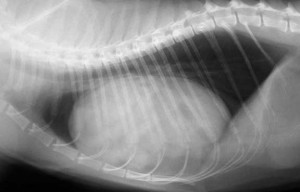

Our physical exam gave us an indication there was a hernia when we palpated the abdomen. To help us confirm the diagnosis we took a radiograph. Radiographs are taken for numerous reasons on every pet that is hit by a car. These pets can have trauma to the chest, broken ribs, herniation of abdominal contents into the chest, and ruptured internal organs like the urinary bladder. The radiograph helps us determine if any of these problems exist. In this case, the radiograph helped verify that Sundance had an abdominal hernia. He also had a fractured pelvis which would heal on its own if he was confined and rested for one month.

In addition to an abdominal hernia, which you will learn more about soon, animals that are hit by cars also can get a diaphragmatic hernia. In this hernia, the abdominal organs like liver or stomach have literally torn through the diaphragm (muscle of respiration) and are sitting in the chest. Needless to say, these are serious injuries. We will show you pictures of this at the end of this page. Lets look at how we make a diagnosis of a diaphragmatic hernia with radiographs.